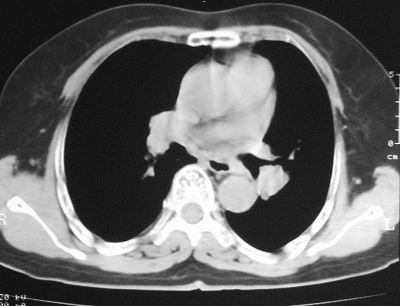

患者,女,64岁,4年前左腮腺"多形性"腺瘤手术治疗史.现复查胸部ct见左下肺块状影,该影与原左腮腺手术是否有联系?

本次复查胸部ct

左下肺癌伴左肺门淋巴结转移

支持考虑左下肺原发性肺癌,并左肺门淋巴结肿大

左下周围型肺癌伴左肺门淋巴结及右肺转移可能性大.

左下肺后基底段实性肿块,周围有毛刺,病变周围有肺气肿,与降主动脉间有条带状影相连,病灶4年前查体发现,纵隔内未见肿大淋巴结。考虑.肺隔离症,建议增强扫描与周围型肺癌鉴别。